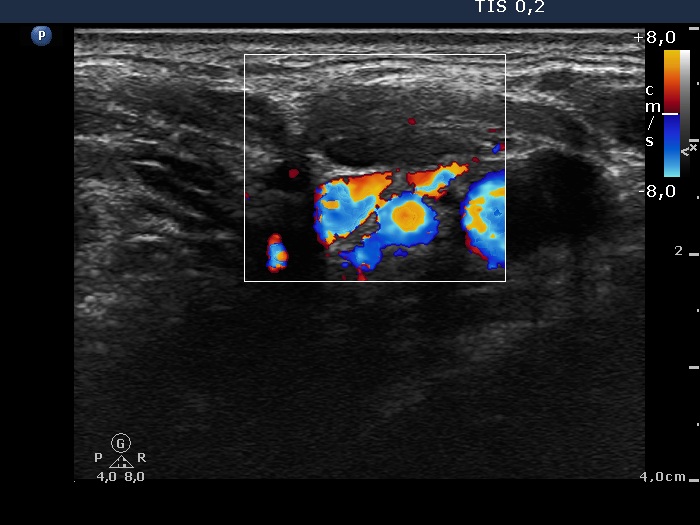

Follow-up examination 8 years later (4th and 5th rows of images):

Ultrasonography revealed hypoechoic discrete lesions in both thyroid lobes. The lesions presented microcalcifications. Corresponding to the palpable mass in the right submandibular region, a reactive-type regular lymph node was found. There was an enlarged lymph node in the left submandibular region. The node had a regular hilum but displayed a heterogeneous pattern.

Cytology was performed from both lymph nodes and from the lesion in the left thyroid bed. FNA resulted in non-diagnostic report from the lesion in the left thyroid bed while cytology of the submandibular lymph nodes showed patterns of a benign, reactive-type lymph node.

Wash-out thyroglobulin levels were 0, 81.1 and 104.9 ng/mL, right submandibular lymph node, left thyroid bed lesion and left submandibular lymph node, respectively.

Histopathology in progress.

Comment. Until the final histological examination is completed, I would like to draw attention to two things. One is the heterogeneity of the left lymph node and the other is the size and structure of the lesions in the thyroid beds - these features are suspicious of thyroid cancer.